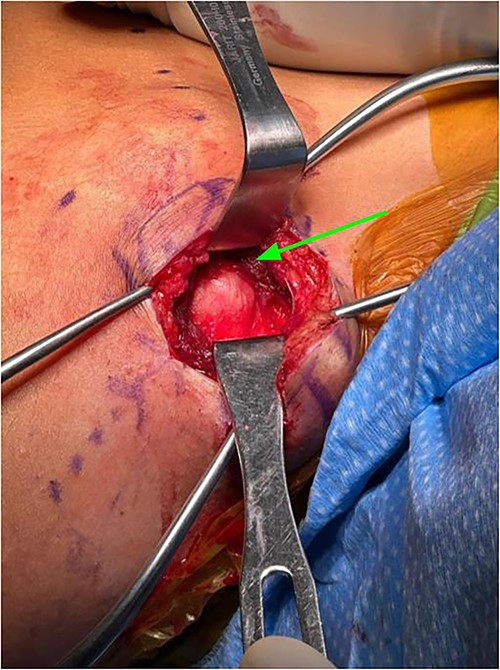

Subcutaneous tissue was divided with the electrocautery. Investing fascia over the trapezius was identified and the division between the superior and middle fibers of the trap was identified. The raphe between the superior and middle fibers was then bluntly spread in line (Fig. 3). We then encountered the superior aspect of the ventral lesion on the scapula (Fig. 4). Of note, the majority of levator scapulae fibers were medial to this lesion; however, the most lateral portion of the muscle was overlying the lesion. These lateral fibers were spread in line to expose the pedunculated mass. Blunt dissection was then taken circumferentially around the stalk of the mass to ensure all soft tissue had been freed from the area (Fig. 5). An osteotome was then carefully placed within the wound at the base of the stalk, and the tumor was then removed and sent to pathology for analysis. The stalk remnant was then filed down to a smooth and stable base with a rasp without any significant areas of potential irritation or prominence. The wound was then copiously irrigated with normal saline. Fluoroscopy images demonstrated complete resection of the bony tumor. There was no active bleeding within the wound. The fascia overlying the trapezius muscle and the skin were then closed.

Exposure after scapula has been retracted and lesion was exposed, lesion can be directly visualized.